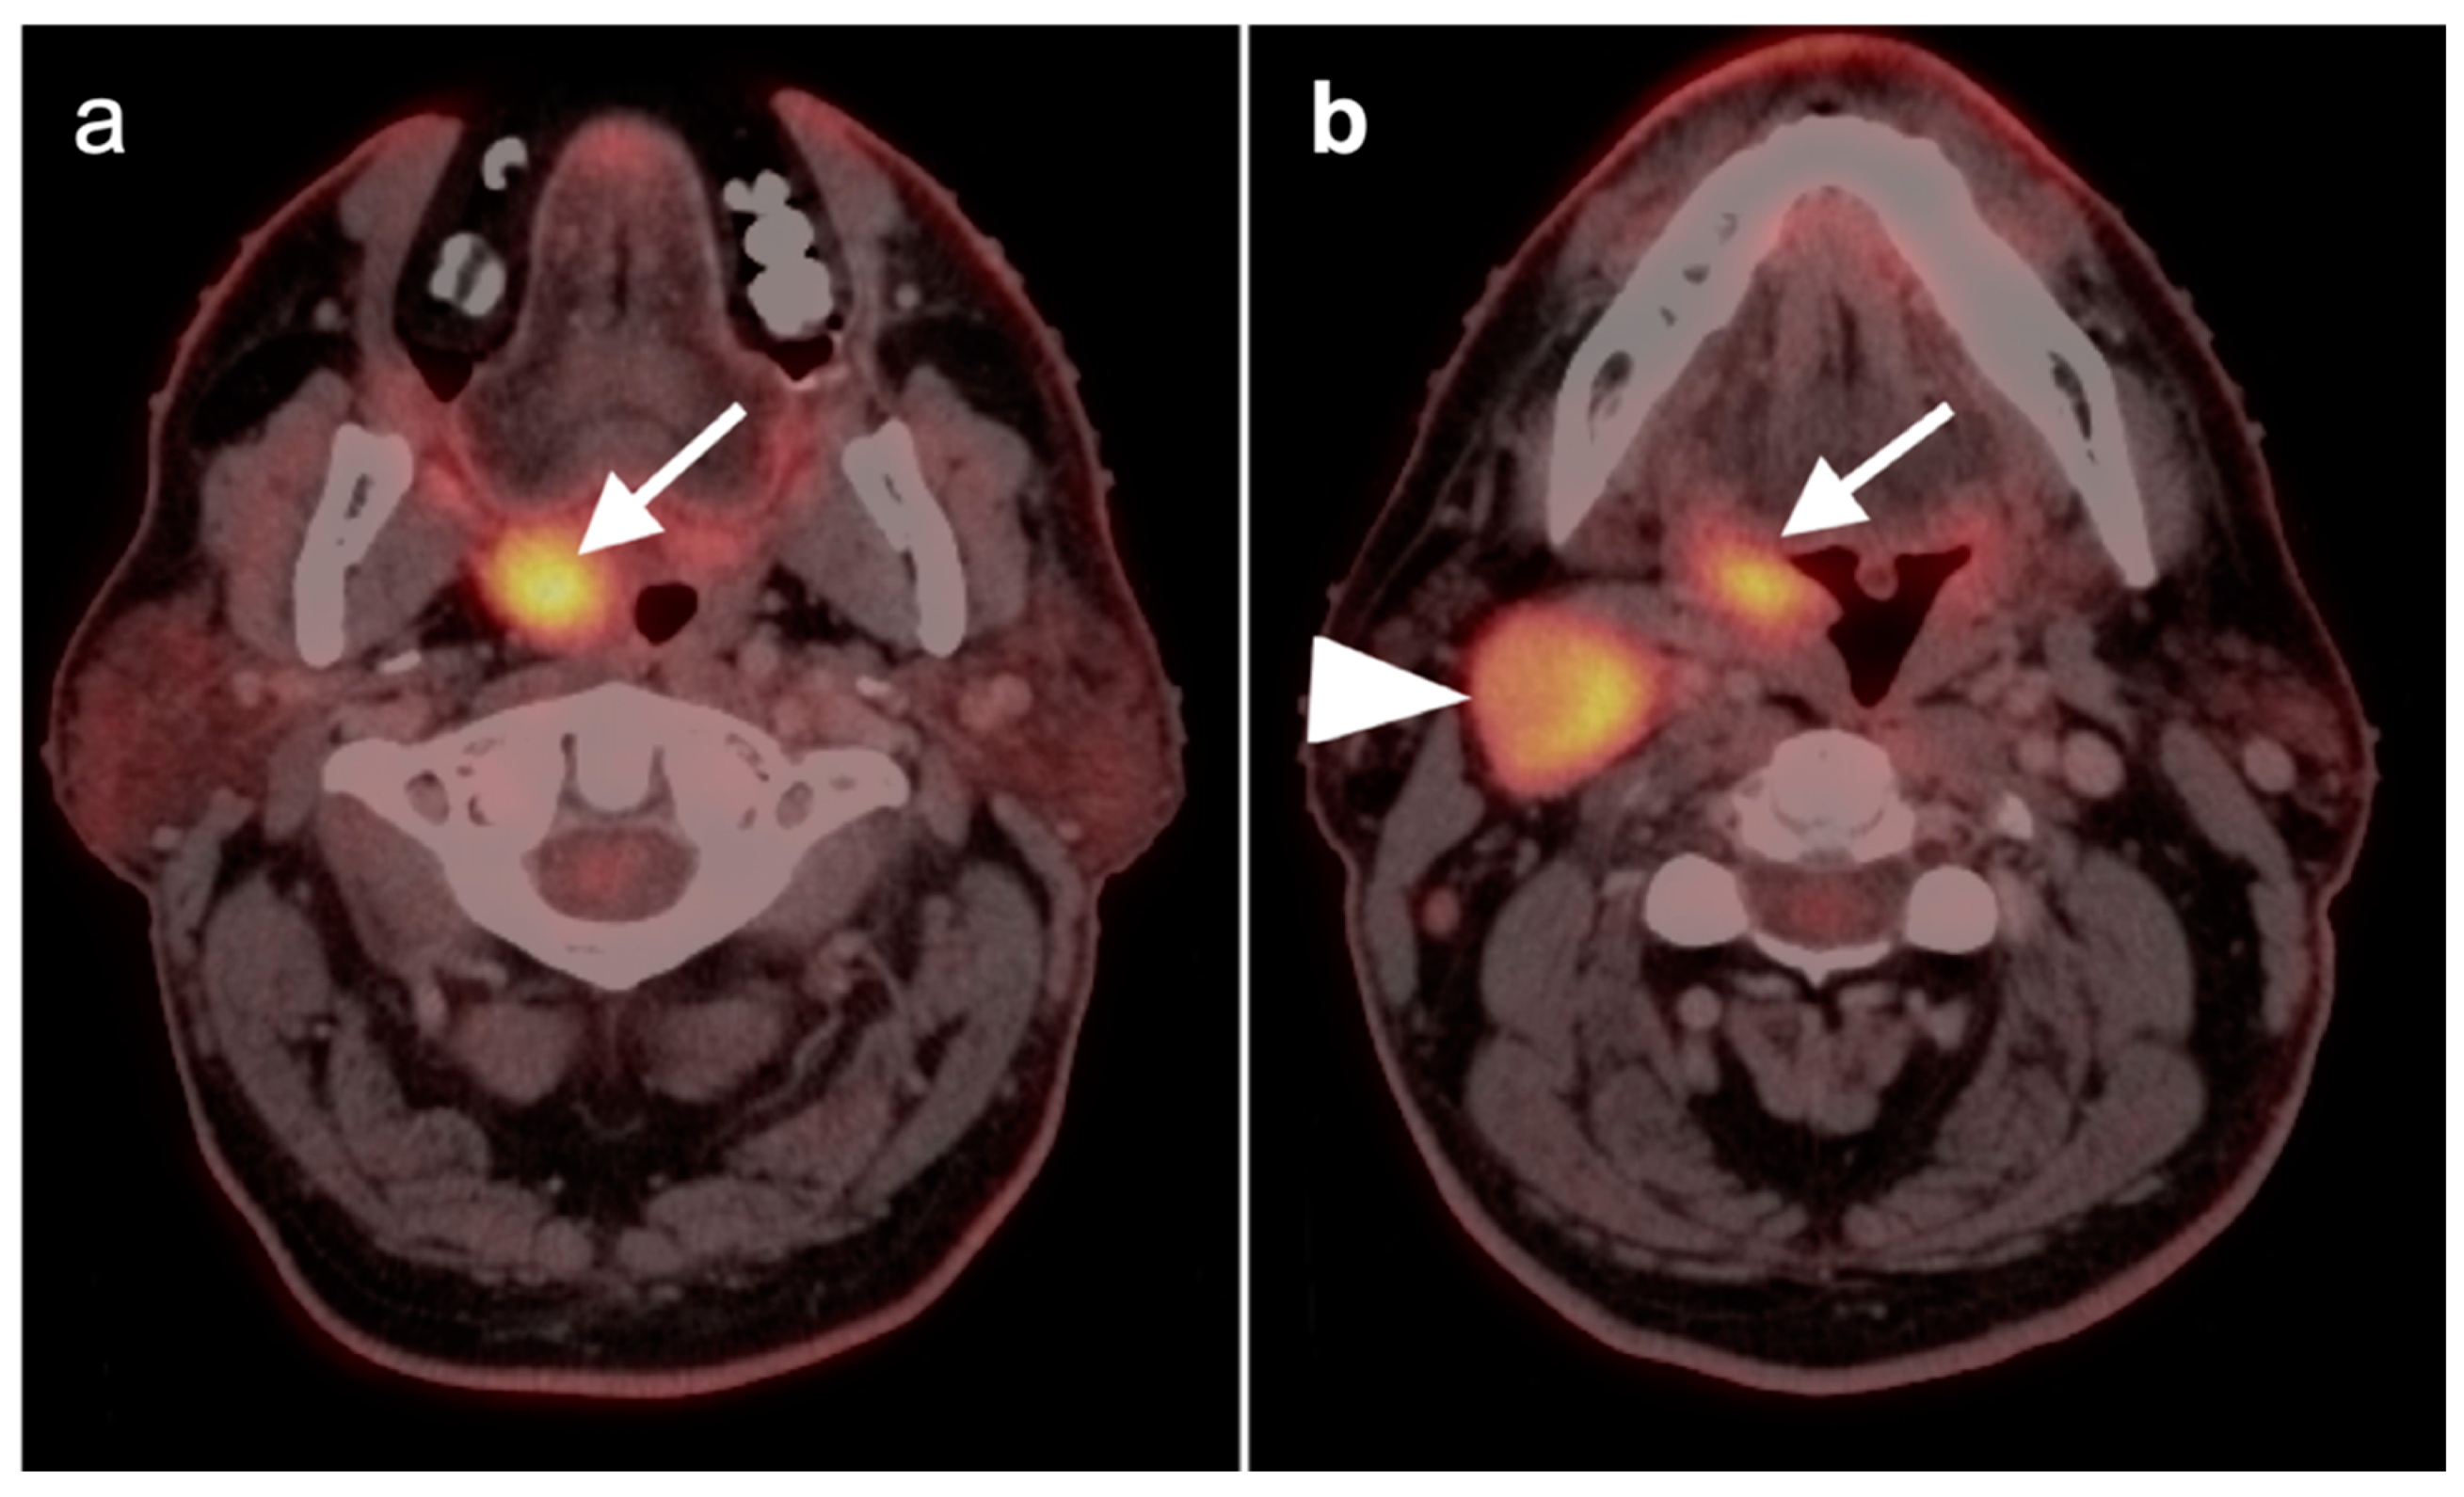

2.3. Nasopharyngeal Carcinoma

- Chen, Y.; Chan, A.T.C.; Le, Q.-T.; Blanchard, P.; Sun, Y.; Ma, J. Nasopharyngeal carcinoma. Lancet 2019, 394, 64–80. [Google Scholar] [CrossRef]

- Ho, F.C.H.; Tham, I.W.K.; Earnest, A.; Lee, K.M.; Lu, J.J. Patterns of regional lymph node metastasis of nasopharyngeal carcinoma: A meta-analysis of clinical evidence. BMC Cancer 2012, 12, 98. [Google Scholar] [CrossRef] [PubMed]

- Huang, C.J.; Leung, S.W.; Lian, S.L.; Wang, C.J.; Fang, F.M.; Ho, Y.H. Patterns of distant metastases in nasopharyngeal carcinoma. Kaohsiung J. Med. Sci. 1996, 12, 229–234. [Google Scholar]

- Chang, M.-C.; Chen, J.-H.; Liang, J.-A.; Yang, K.-T.; Cheng, K.-Y.; Kao, C.-H. Accuracy of whole-body FDG-PET and FDG-PET/CT in M staging of nasopharyngeal carcinoma: A systematic review and meta-analysis. Eur. J. Radiol. 2013, 82, 366–373. [Google Scholar] [CrossRef]

- Mohandas, A.; Marcus, C.; Kang, H.; Truong, M.-T.; Subramaniam, R.M. FDG PET/CT in the management of nasopharyngeal carcinoma. AJR Am. J. Roentgenol. 2014, 203, W146–W157. [Google Scholar] [CrossRef]

- Liu, T.; Xu, W.; Yan, W.-L.; Ye, M.; Bai, Y.-R.; Huang, G. FDG-PET, CT, MRI for diagnosis of local residual or recurrent nasopharyngeal carcinoma, which one is the best? A systematic review. Radiother. Oncol. 2007, 85, 327–335. [Google Scholar] [CrossRef] [PubMed]